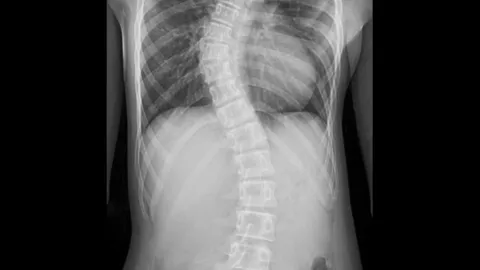

แม่แชร์ประสบการณ์ ลูก 11 ขวบ ผ่าตัดกระดูกสันหลังคด หมอบอกเด็กป่วยเยอะ